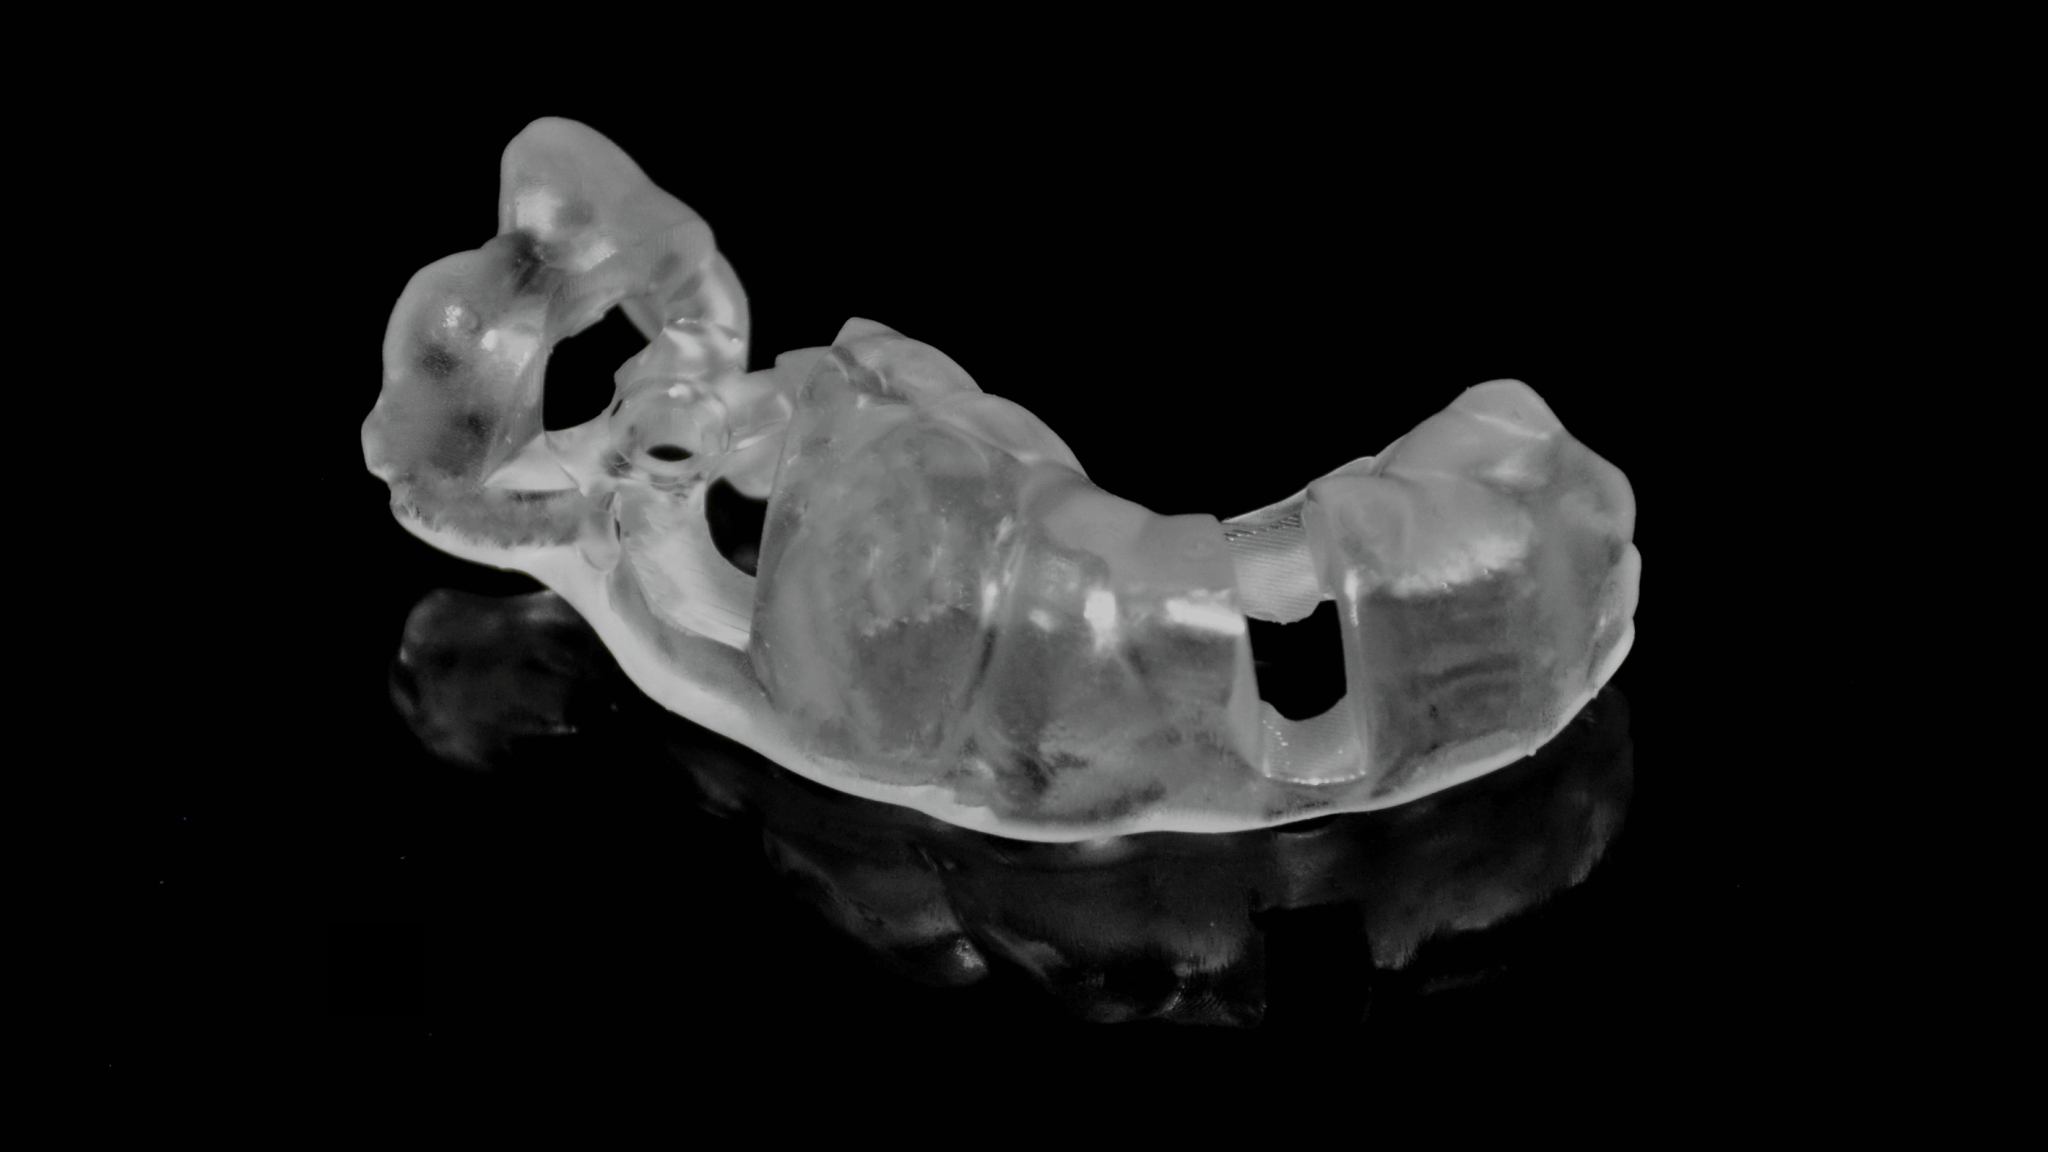

4. Print model & guide with AccuFab-D1

Printed guide

Try-in on the printed model